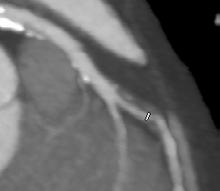

Imagistica cardiacă – rol, metode și perspective

Conf. Univ. Dr. Bogdan Popa

Conceptul de placă de aterom vulnerabilă – cum este integrat în noua paradigmă de stratificare a riscului de eveniment coronarian acut și care este rolul examinării CT coronariene

Dr. Ofelia Niță